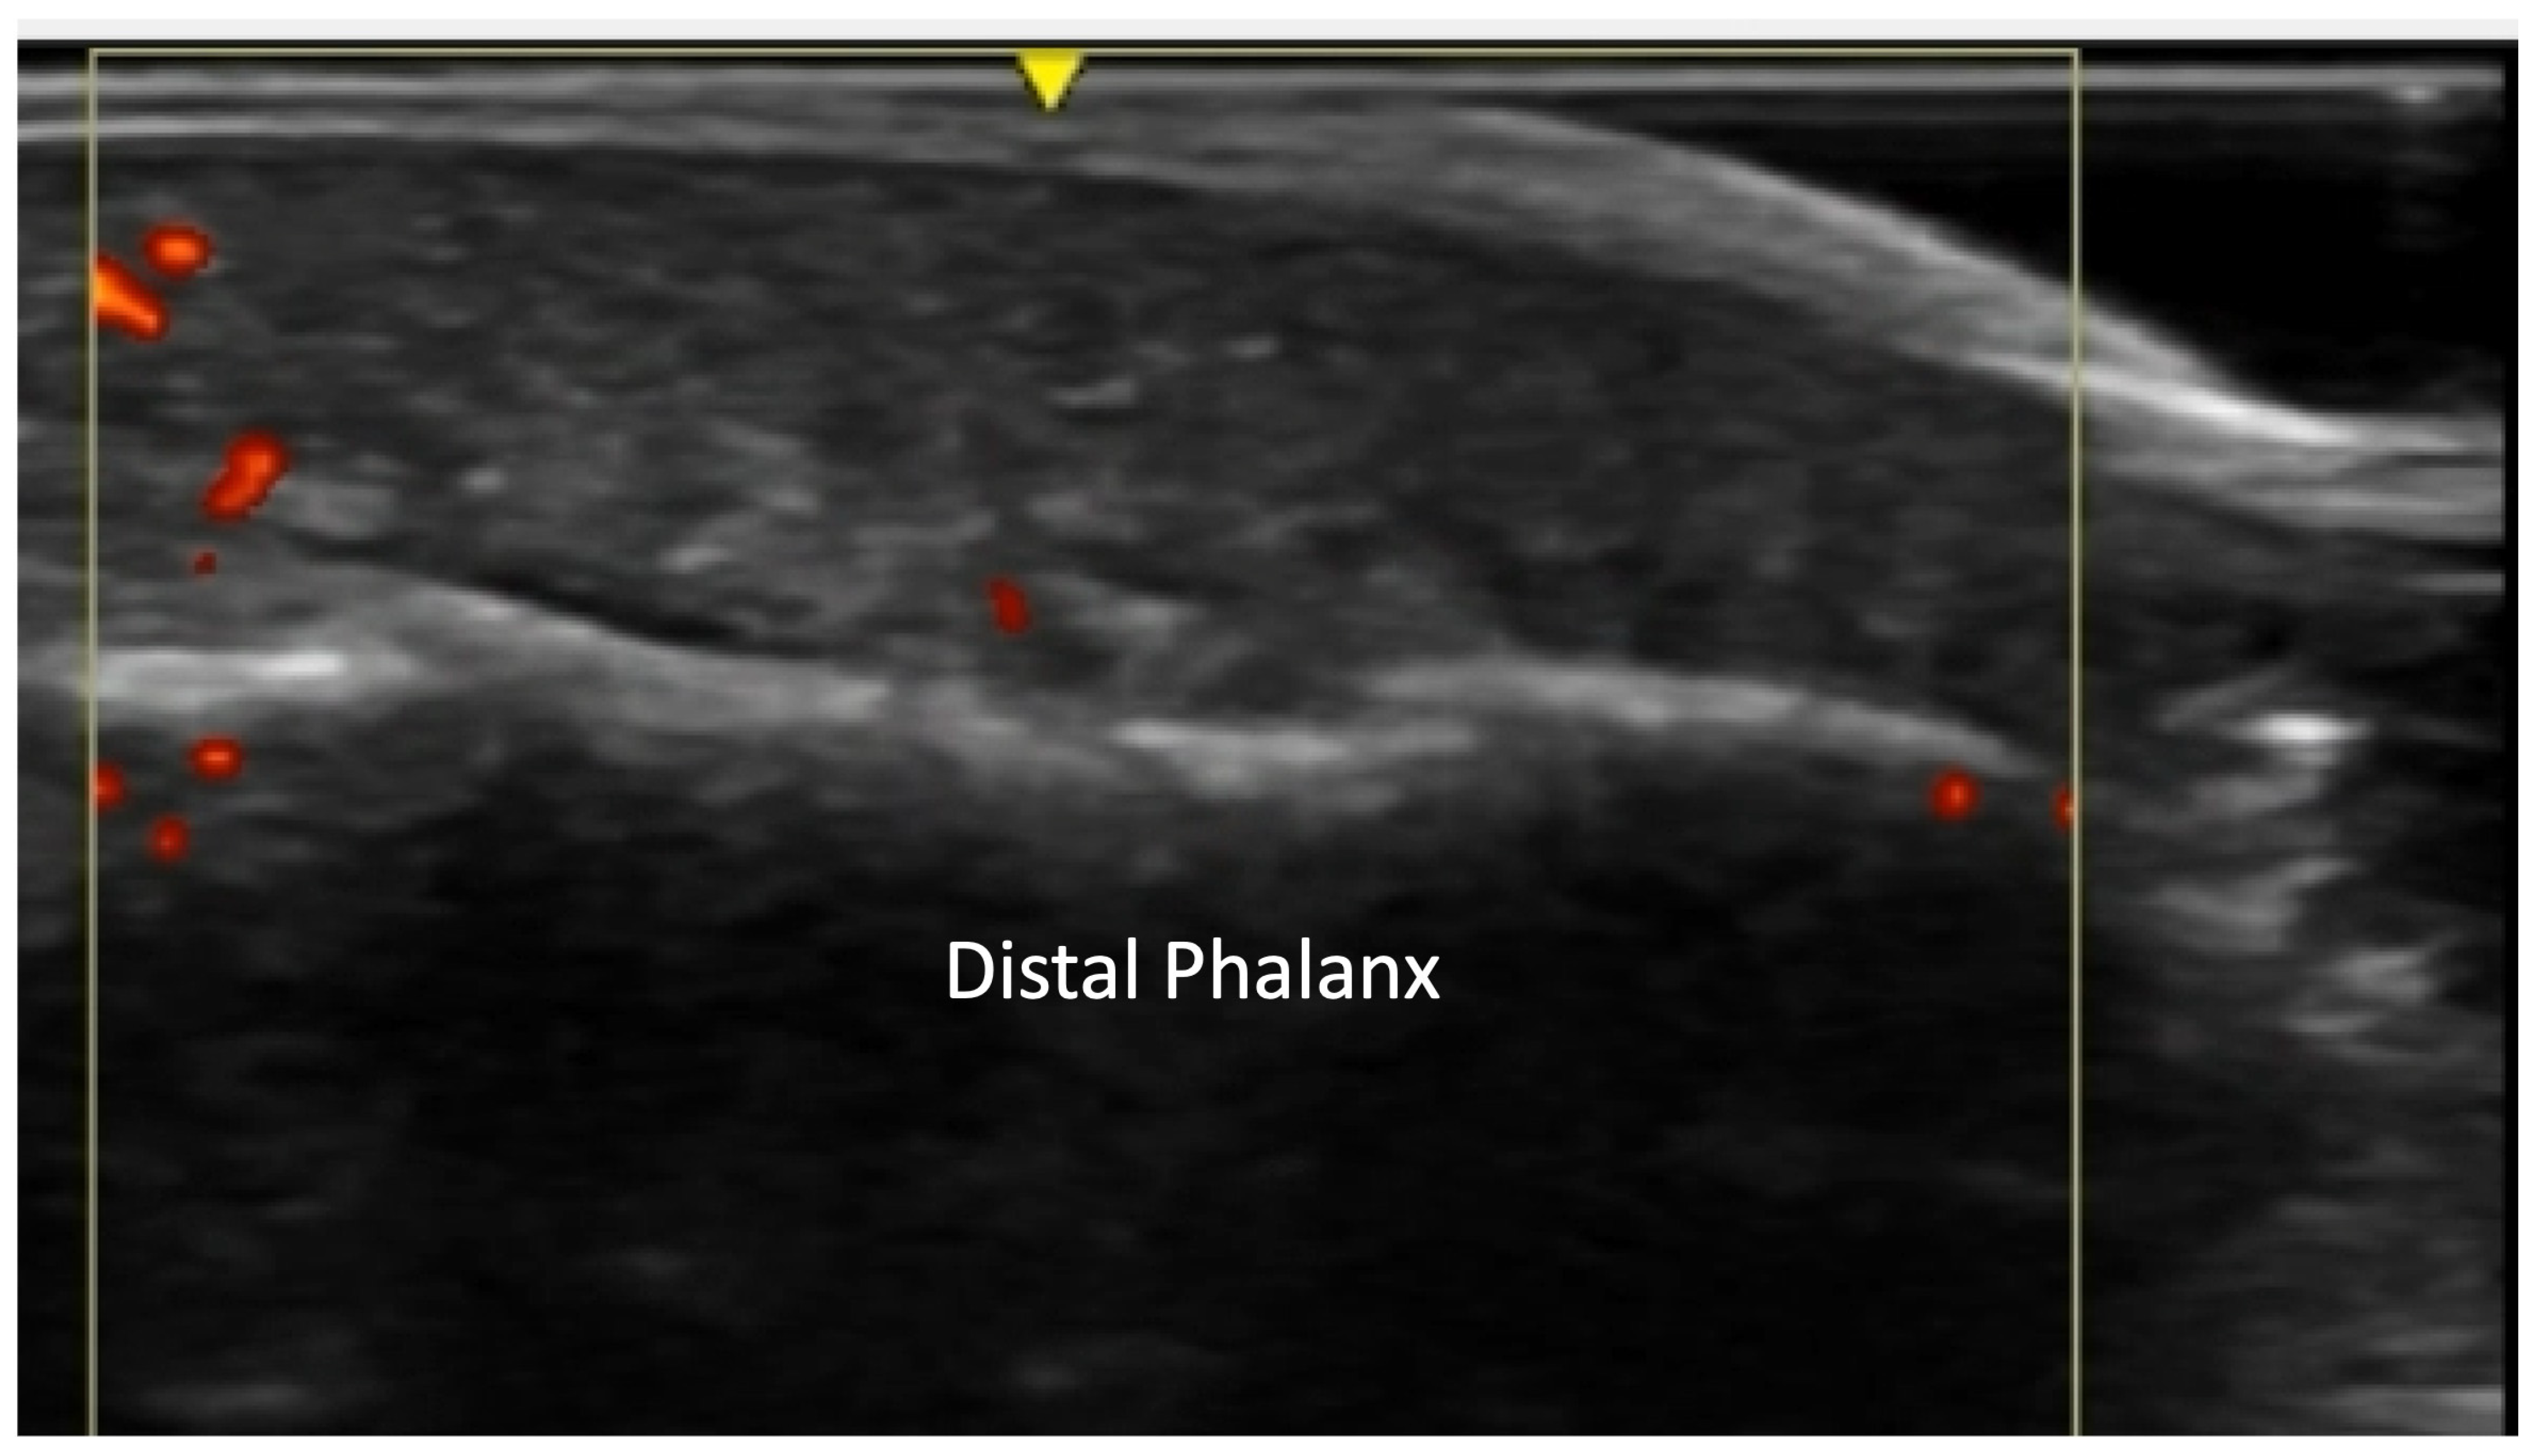

2.1.3. Acro-Osteolysis

4.1. Evaluation of the Fingers

4.1.1. Dorsal Aspect